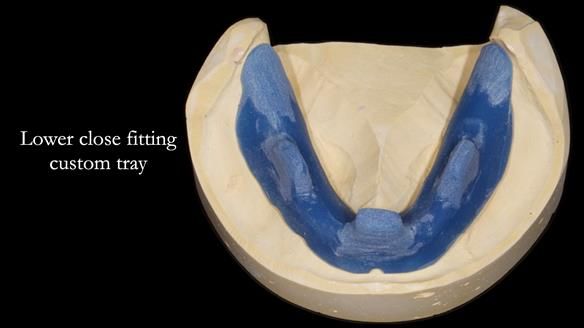

In this edition, I present the complete denture treatment for Kate, a 69-year-old American woman living in Garstang, UK. Kate had been edentulous for many years and required a set of complete dentures that closely mimicked her natural teeth. The new upper and lower dentures provided excellent retention and stability, with significant suction in the upper denture. Below, I detail the step-by-step process of her treatment, as well as my workflow for implant-supported overdentures for patients who may require them.

Treatment Process: I provided the clinical work while Rowan Garstang and Sam Hesketh delivered the technical aspects. The treatment required fifteen visits to fit and review Edgar.